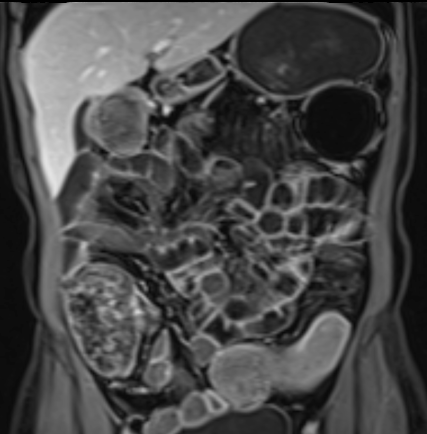

Bệnh nhân nữ 48 tuổi, đang điều trị bằng thuốc kháng TNF, được chỉ định nội soi đại tràng.

Phát hiện hẹp lòng ruột ở đại tràng sigma, không thể vượt qua được khi nội soi.

MR-enterography được thực hiện để đánh giá mức độ lan rộng của chỗ hẹp.

Cuộn qua các hình ảnh.

Ruột non bình thường, nhưng ghi nhận các đoạn hẹp ở đại tràng xuống và đại tràng ngang.

Cả hai đoạn hẹp đều có thành ruột dày đến 8 mm và ngấm thuốc rõ rệt theo kiểu niêm mạc ở đại tràng xuống và kiểu phân lớp ở đại tràng ngang.

Giãn ruột trước chỗ hẹp được ghi nhận ở cả hai đoạn.

Do các chỗ hẹp này không hiện diện khi nội soi đại tràng trước khi điều trị kháng TNF, nhiều khả năng chúng đã hình thành trong quá trình điều trị.

Do đó, quyết định phẫu thuật cắt đại tràng gần toàn bộ với miệng nối hồi-sigma đã được đưa ra.